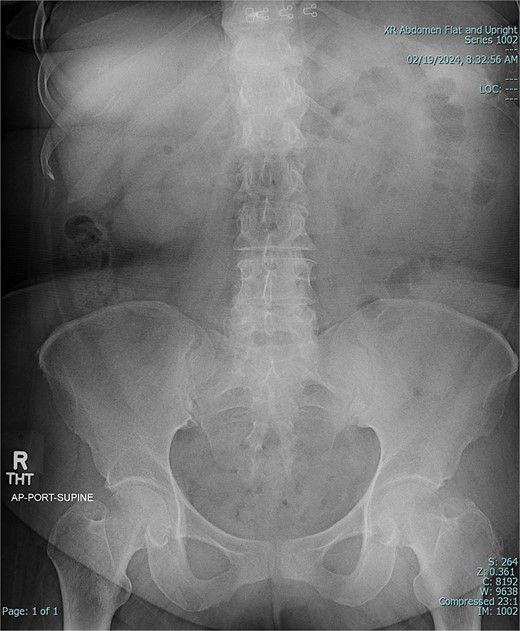

A 67-year-old female patient with a past medical history significant only for C-section, presented with 1 week of intermittent abdominal pain, distension, and nausea with vomiting. Vital signs were in the normal range. Physical exam was notable for a soft and nondistended abdomen with right lower quadrant tenderness. Laboratory studies were unremarkable. Radiological imaging (Figs 1 and 2) demonstrated a developing SBO.

Preoperative X-ray of abdomen, demonstrating small bowel obstruction.